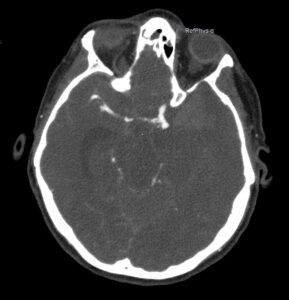

Angio-TC craneal